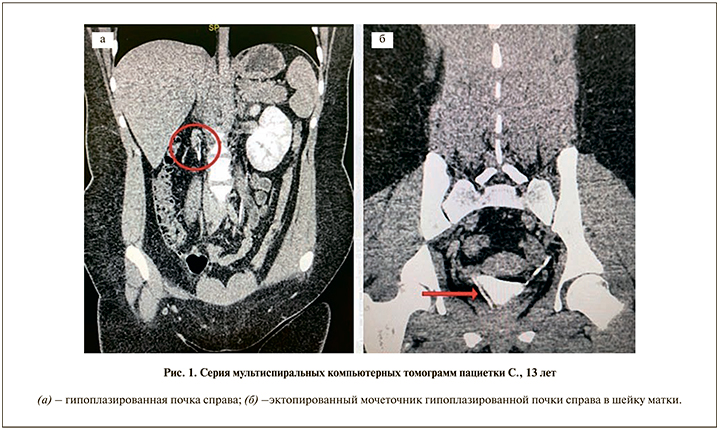

Объективно: рост – 154 см, масса тела – 82 кг. Ребенок был общеклинически обследован, выполнены общеклинические анализы, УЗИ почек и мочевыводящих путей, КТ почек и мочевыводящих путей (двухэнергетическое сканирование) с контрастированием, проба с индигокармином, цистоскопия и кольпоскопия. По результатам УЗИ выявлены признаки диффузных паренхиматозных изменений левой почки, аплазии правой почки. По данным КТ определяется гипоплазированная правая почка неправильной формы, без структурной дифференцировки размером 15х9х25 мм, локализованная паравертебрально на уровне тела L1. В артериальную фазу в проекции данной почки отмечаются участки накопления контрастного аналогично корковому веществу почки. В экскреторную фазу (на 10-й минуте) визуализируется правый мочеточник диаметром до 1,7–2 мм, удвоенный в верхней трети (на протяжении 20 мм), ход мочеточника прослеживается фрагментарно, устья в область шейки матки. При повторном сканировании экскреторной фазы (на 60-й минуте) визуализируется контраст в просвете шейки матки и в просвете влагалища (рис. 1). Ребенку выполнена проба с индигокармином: в мочевой пузырь установлен уретральный катетер Нелатона ch8, через который в мочевой пузырь введен индигокармин 10 мл, уретральный катетер удален, через 30 мин на урологической прокладке визуализирована только светло-желтая моча, свидетельствующая об эктопии мочеточника. Выполнена цистоскопия, по данным которой слизистая мочевого пузыря без признаков воспаления, устье левого мочеточника расположено физиологически, не зияет, устье правого мочеточника не обнаружено. Также ребенку выполнена кольпоскопия, по данным которой слизистая без особенностей, дополнительных образований не выявлено.